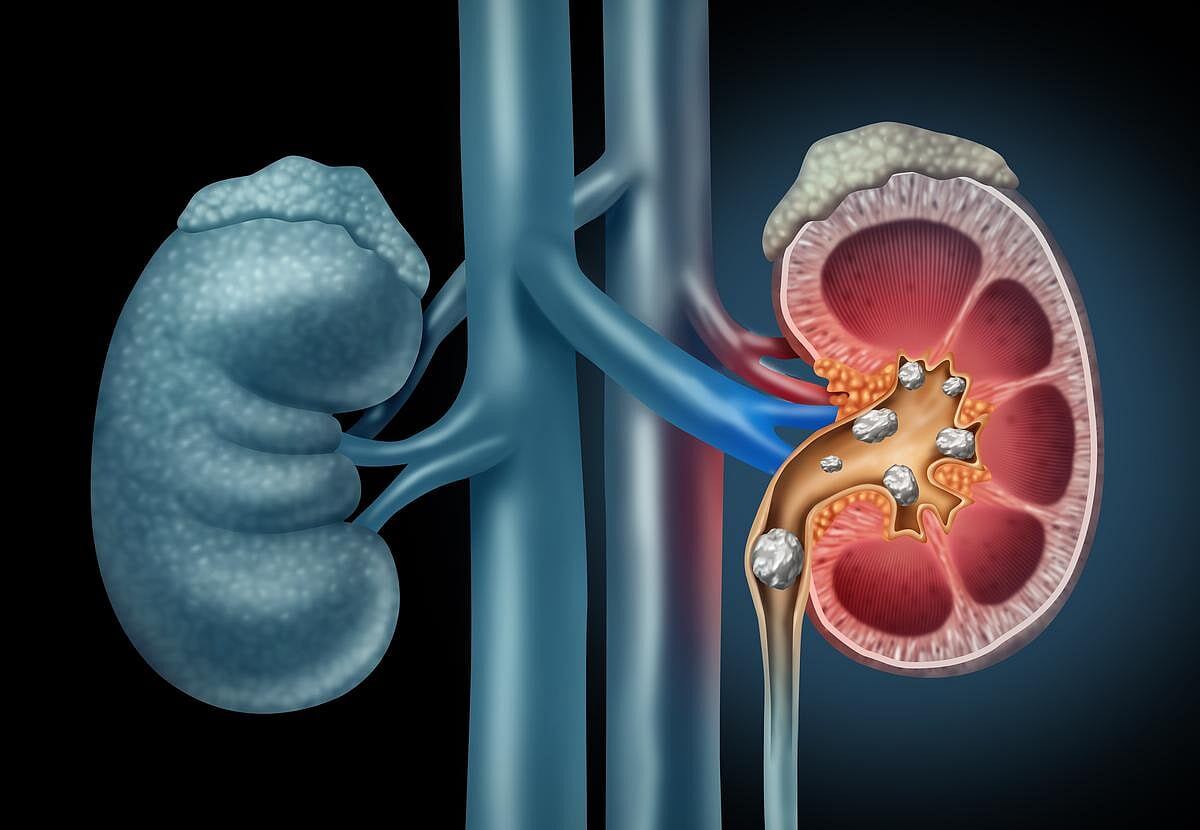

Los cálculos renales son bultos duros que se desarrollan a partir de los minerales y químicos presentes en la orina, según la Fundación Nacional del Riñón.

Las personas que desarrollan cálculos renales pueden sufrir dolores extremos en el costado o la espalda, sangre en la orina, náuseas o vómitos, o fiebre y escalofríos, según la fundación.

Aproximadamente 1 de cada 11 personas en EE. UU. se ve afectada por cálculos renales, y casi la mitad los experimentará más de una vez, según los investigadores en notas de fondo.

Las piedras se forman con mayor facilidad cuando las personas no beben suficiente agua y su orina se concentra, según la fundación.